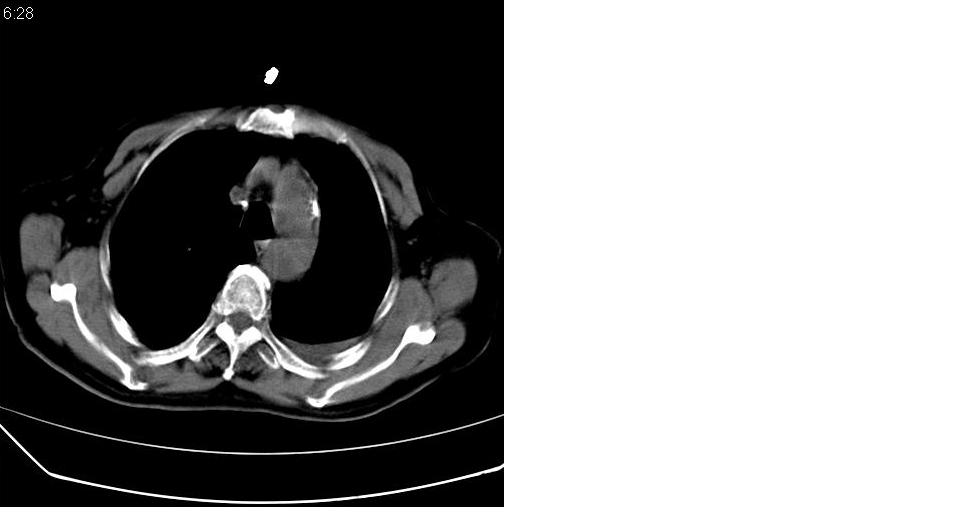

左肺下叶略萎陷、实变,内可见含气支气管征。左舌叶、中叶亦见少许斑片状高密度区,边界不清。纵隔未见肿大淋巴结影。

考虑:1、肺感染;

2、建议严格抗炎治疗后复查。

左下肺体积缩小,密度增高,见片增密影。边界模糊,见支气管充气像,肺门纵隔无异示,心脏气管左移,左侧胸腔少量积液。考虑肺部感染伴部分肺不张[有脑梗塞病史坠积性肺炎可能]

1、左肺下叶后基底段炎症并膨胀不全。

2、左侧胸腔积液。

左肺下叶体积缩小,成类楔形软组织影,其内可见部分含气支气管影,相应左侧肺门区未见明显肿块,考虑炎性病变,建议抗炎后短期复查